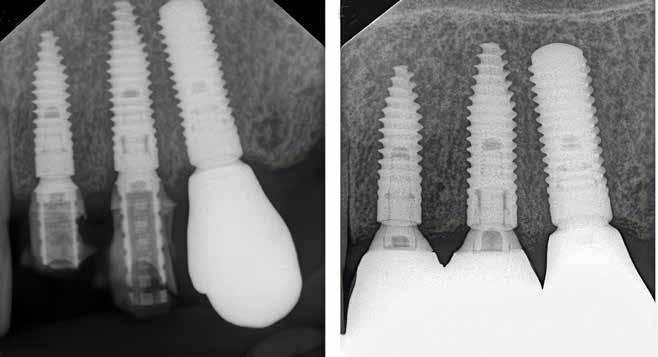

Klik ind på Tandlægebladet.dk og opret en reklamation, så sørger vi for, at bladet lander i din postkasse.

Klik ind på Tandlægebladet.dk og vælg om os

BAGGRUND – Transverselle okklusionsafvigelser kombineret med en vækstbetinget kæbedeformitet korrigeres sædvanligvis ved en sektioneret Le Fort 1-osteotomi eller kirurgisk assisteret ganeekspansion. Ved ekstreme transverselle skeletale diskrepanser mellem maksillen og mandiblen kan der være indikation for transversel udvidelse af mandiblen ved hjælp af mandibulær midtlinjeosteotomi eller mandibulær midtlinjedistraktionsosteogenese.

PATIENTTILFÆLDE – En 15-årig dreng med infantil autisme blev henvist fra Hjørring Kommunes Tandpleje til Kæbekirurgisk Afdeling, Aalborg Universitetshospital, for ortodontisk-kirurgisk behandling af et stort horisontalt maksillært overbid uden kontakt på nogen af tænderne. Den vækstbetingede kæbedeformitet blev korrigeret ved hjælp af ortodonti og mandibulær midtlinjedistraktionsosteogenese efterfulgt af en sektioneret Le Fort I-osteotomi og bilateral sagittal splitosteotomi.

KONKLUSION – Mandibulær midtlinjedistraktionsosteogenese er en forudsigelig behandlingsmodalitet til transversel udvidelse af mandiblen. Imidlertid er behandlingen forbundet med en betydelig risiko for recidiv samt biologiske og tekniske komplikationer, hvorfor mandibulær midtlinjedistraktionsosteogenese udelukkende anbefales til korrektion af ekstreme vækstbetingede transverselle okklusionsafvigelser.

EMNEORD Jaw abnormalities | malocclusion | orthodontics | orthognathic surgery

PERNILLE SAGBAKKEN, tandlæge, Odontologisk Institut, Det Sundhedsvidenskabelige Fakultet, Københavns Universitet

ANNETTE DALGAARD KJELLERUP, specialtandlæge i ortodonti, Kæbekirurgisk Afdeling, Aalborg Universitetshospital

THOMAS STARCH-JENSEN, klinisk professor, overtandlæge, specialtandlæge i tand-, mund- og kæbekirurgi, postgraduat klinisk lektor, ph.d., Kæbekirurgisk Afdeling, Aalborg Universitetshospital, og Klinisk Institut, Det Sundhedsvidenskabelige Fakultet, Aalborg Universitet

Accepteret til publikation den 12. december 2024.